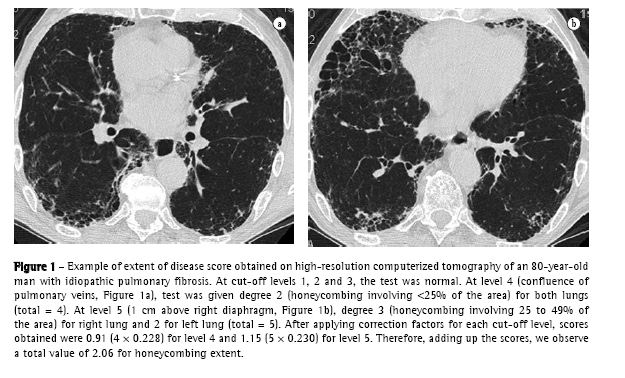

In the end, TID, reticular abnormality/honeycombing and ground-glass opacity levels were obtained by totaling the scores for each level. An example of how these scores were obtained is shown in Figure 1.

c) the following technique was used for HRCT: GE equipment, HISPEED model; 1-mm thick slices, at 1.5 s intervals and increased by 10 mm; image reconstruction with a 512 × 512 pixel matrix, using a high resolution algorithm; 1000 HU width window; −700 HU medium window level. Interpretation of tomographic findings was performed according to a consensus among four radiologists with extensive experience in interstitial disease. In the absence of histologic material, the diagnosis of IPF by HRCT was accepted only upon concordance of all readers and if all clinical and functional criteria described above were met. An initial overall analysis of the HRCT (without considering cut-off levels) was conducted, in search of the following findings: nodules, ground-glass opacities, reticular abnormality, honeycombing (cysts  3 mm and  3 mm), traction bronchiectasis, air trapping areas and emphysema.(18,19) Subsequently, the HRCT was evaluated as to the extent and intensity of interstitial lung involvement, considering five cut-off levels: 1) origin of major vessels; 2) aortic arch level; 3) carina; 4) confluence of pulmonary veins; and 5) 1 cm above the right diaphragm.(6,19-21) Using a semiquantitative evaluation system, each of these levels (right and left, separately, totaling 10 levels) was analyzed as to the following aspects:

Score of extent of reticular abnormality and honeycombing:

0) no reticular abnormality or honeycombing;

1) reticular abnormality and no honeycombing;

2) honeycombing (with or without reticular abnormality) involving  25% of the area;

3) honeycombing involving 25-49% of the area;

4) honeycombing involving 50-75% of the area; and

5) honeycombing involving  75% of the area.(10,22,23)

For the analysis of HRCT findings, estimated pulmonary involvement was obtained using an influence factor ('weight') to correct different pulmonary volumes at each level, as follows(19):

origin of major vessels - weight = 0.129;

aortic arch level - weight = 0.190;

carina - weight = 0.222;

confluence of pulmonary veins - weight = 0.228; and

1 cm above the right diaphragm weight = 0.230.